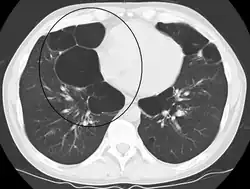

A CT scan is not routinely used except for the exclusion of bronchiectasis.[5] Pulse oximetry measurement of peripheral oxygen saturation is recommended in people with clinical signs of respiratory failure or right heart failure.[5] An analysis of arterial blood is recommended in those with a peripheral oxygen saturation of 92% or less to determine actual blood oxygen level and assess for high levels of carbon dioxide in the blood, which may have therapeutic implications such as need for non-invasive ventilation or oxygen supplementation.[10] WHO recommends that all those diagnosed with COPD be screened for alpha-1 antitrypsin deficiency.[40]

A severe case of bullous emphysema -

Axial CT image of the lung of a person with end-stage bullous emphysema -